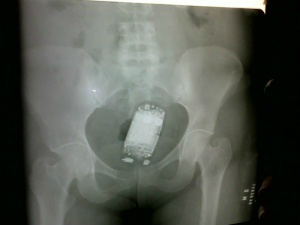

O texto prevê que todo visitante será revistado de forma mecânica, sendo dispensados gestantes e portadores de marca-passos. De forma excepcional, a revista manual será realizada em caso de fundada suspeita de que o visitante traga consigo objetos, produtos ou substâncias proibidas.

“A revista manual é vexatória. O ideal é a utilização de detectores de metais e aparelhos de raio-x, por preservar a integridade psicológica e moral da pessoa revistada. As mulheres se expõem inadequadamente e inutilmente, uma vez que há alternativas para fazer a revista de forma mais humana, sem ferir a integridade dessas pessoas”, afirma o presidente da OAB, Júlio Cesar Souza Rodrigues.